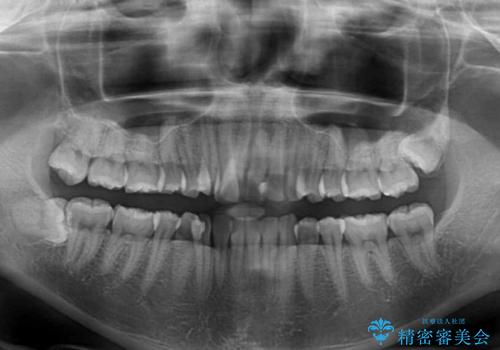

右上前から2番目の歯が内側に転位しているため、上顎の正中は右にずれていました。

右上4番目の歯を抜歯し、上顎裏側に補助装置を装着して左の歯列全体を後方に移動させながら、正中を合わせるようにして行くこととしました。

元々神経の失活してしまっている前歯2本は変色が目立つようになってきたため、今後セラミッククラウンによる補綴治療を行う予定です。